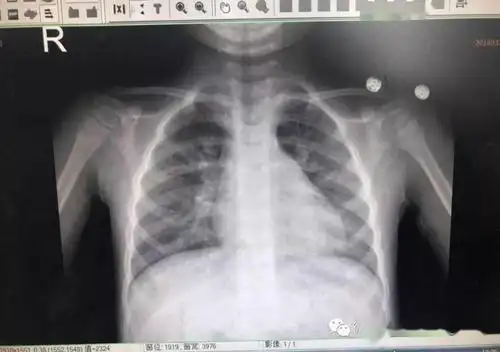

宗医师说 | 谁说小儿推拿不能治疗肺炎?用临床效果来啪啪打脸!